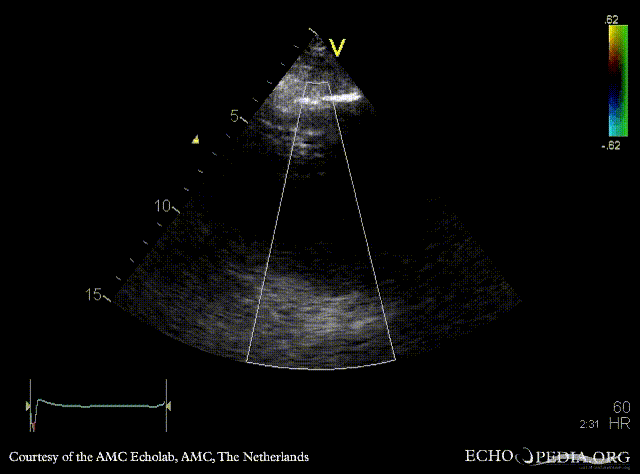

| PSAX: Color Doppler: coronary fistula | A4CH |